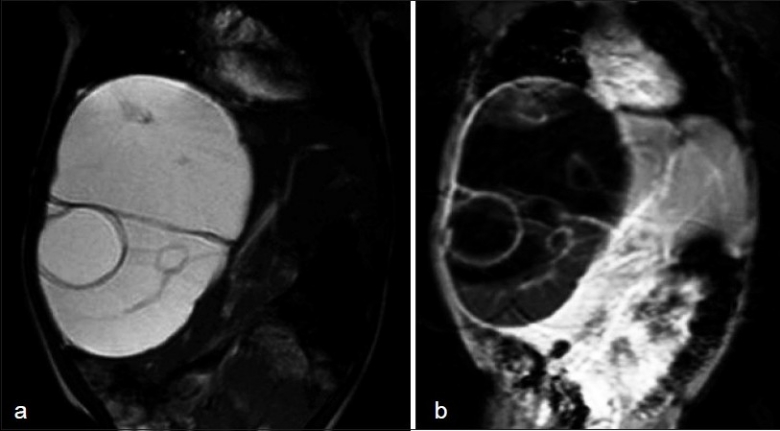

On an MRI scan, the lesion was hyper intense on T2W image and hypo intense on T1W images – conforming its cystic nature. Multiple septa were best seen on T2 W images, which demonstrated the complex nature of the cystic mass [Figure 1a and andbb].

| Figure 1 (a) MRI Abdomen (T2 weighted image), (b) MRI Abdomen (T1 weighted image)